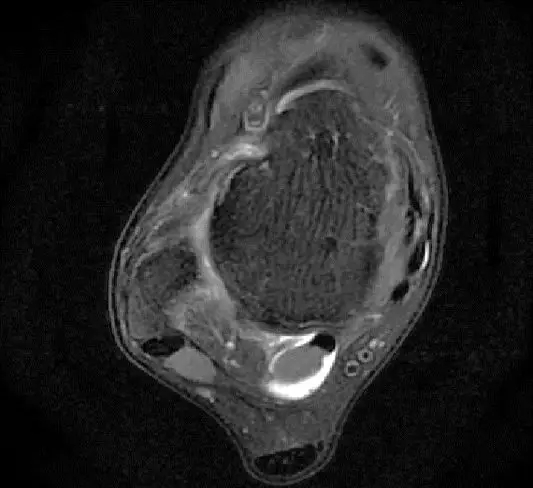

此片可以看到韧带结构消失,T2相高信号,整体韧带增粗,松弛,腓骨肌腱内侧,跟绯肌腱的形态完全消失,它的韧带也是松弛增粗的。所以考虑是踝关节距腓前韧带的损伤。